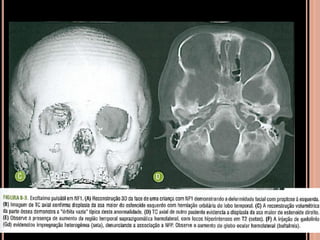

 Displasia de asa maior do esfenoide: típica mas

incomum; exoftamo pulsátil (herniação meníngea,

espaço liquórico ou lobo temporal); isolado ou

associado e neurofibroma plexiforme na

distribuição trigeminal;